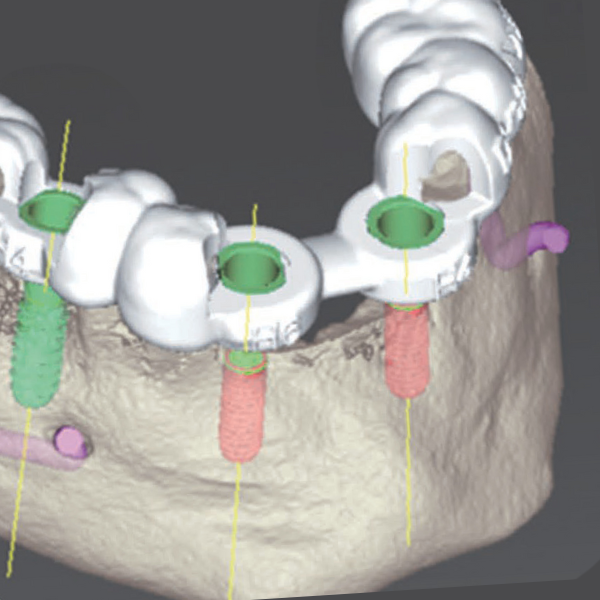

手術の安全性と精度を高めるため、当院ではCTスキャンを活用しています。インプラント治療は、人工の歯根(インプラント体)をあごの骨に埋め込む治療です。あごの骨には神経や血管が通っているため、これらを傷つけないよう慎重な計画が必要です。

CTスキャンは、一般的な二次元レントゲンとは異なり、骨の構造を三次元で確認できるため、あごの骨内の神経や血管の正確な位置を把握することが可能です。これにより、より正確で安全な治療計画を立てることができます。

シミュレーションソフト

CTスキャンで取得した詳細なデータをコンピュータに取り込み、専用のシミュレーションソフトで綿密に解析します。

この解析により、インプラントの最適な大きさ、正確な埋入位置、適切な埋入角度を判断し、術前に具体的な手術計画を立てます。

2つの3Dシミュレーション

2つの3Dシミュレーションソフトを使用し、多角的、立体的に準備を進めます。当院では、経験豊富な設計のプロと一緒に万全のインプラント設計計画を立てており、可能な限り事前に患者様への不安と取り除くよう努めております。